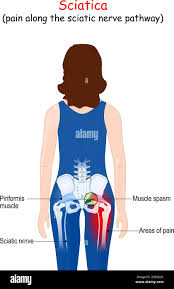

Download Sciatic nerve pain pictures